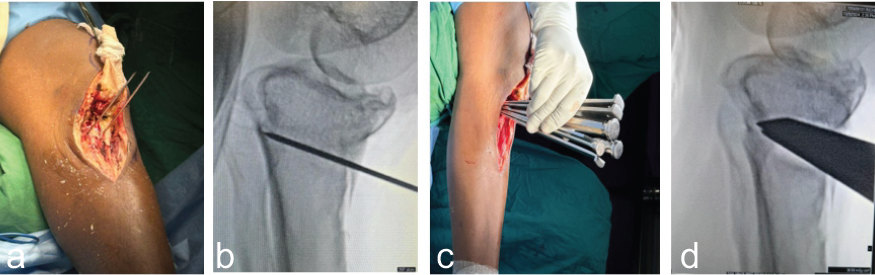

A midline skin incision was made slightly medial to the tibial tuberosity, beginning at the level of the inferior patellar pole and extending approximately 10 cm distally. Full-thickness subcutaneous flaps were carefully elevated on both medial and lateral sides. On the medial side, subperiosteal dissection was carried out beneath the medial collateral ligament extending to the posteromedial aspect of the proximal tibia. Laterally, the tibialis anterior muscle was elevated from the tibial surface (Fig. 3a). The patellar tendon insertion was clearly identified, and the tibial tuberosity was exposed. An osteotomy line was marked along the anterior tibial crest, extending about 7 cm distally on both sides of the tibial tubercle, followed using a power saw to cut a bone block (Fig. 3b).

Figure 3: Left knee. (a) Exposure of tibial tuberosity with elevation of full thickness flap medially and laterally and (b) osteotomy of the tibial tubercle using saw.

A 7-cm segment of the tibial tubercle, maintaining appropriate width and thickness, was mobilized, along with the attached patellar tendon as a single unit. This segment was wrapped in gauze soaked with vancomycin and retracted proximally for protection (Fig. 4a). With the knee flexed to 30° and posteriorly supported, a C-arm was used to obtain a lateral fluoroscopic view. The proximal tibial osteotomy site was identified 3 cm below the joint line. Two parallel monocortical K-wires were inserted obliquely under fluoroscopic guidance, starting from distal to proximal along the visible previous fracture line and parallel to posterior tibial slope, either side of the tibial tubercle bed. These wires were advanced until they abutted the posterior tibial cortex, aiming for a point ending with previous fracture line, approximately 2.5 cm distal to the joint line, as verified by fluoroscopy (Fig. 4a and b). After the osteotomy lines were completed using a power saw, osteotomes were gently used to reach close-within approximately 5 mm-to the posterior cortex across the full transverse diameter of the tibia. Care was taken to preserve the posterior cortex and avoid fracture propagation. To facilitate controlled opening of the osteotomy, multiple 2.5 mm drill holes were placed at the intended hinge area in the posterior cortex to soften it. Multiple stacked osteotome was introduced anteriorly to gradually open the osteotomy site (Fig. 4c and d).

Figure 4: Left knee. (a and b) Intraoperative and fluoroscopic image insertion of two parallel guide wires along the previous fracture line and (c and d) intraoperative and fluoroscopic image of stacked osteotomes used for opening the desired wedge.